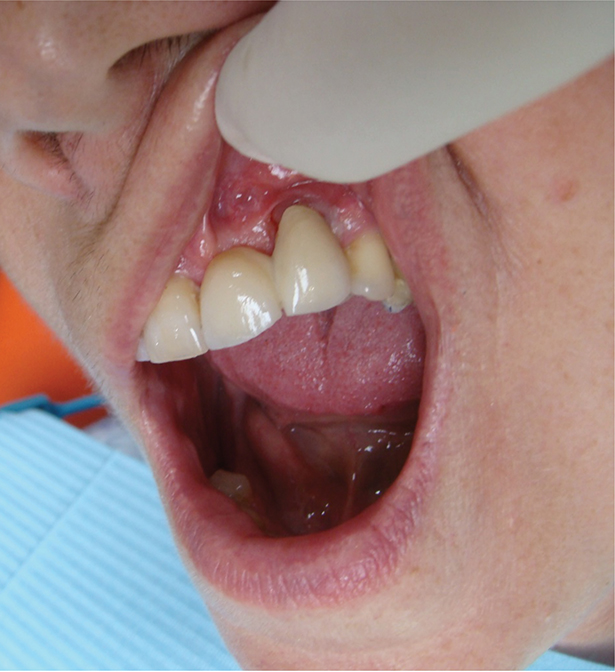

Above: Surgically driven implant placement leading to an aesthetic compromise.

Above: Poor aesthetic outcome of the final restoration.